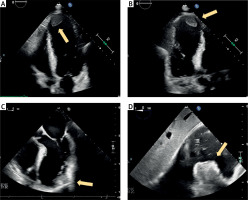

Figure 1

Echocardiographic diagnosis of the left ventricular aneurysm located in the apical anterior wall with evidence of thrombotic material. A – Transthoracic echocardiography in the 4-chamber view showing the aneurysm. B – Transthoracic echocardiography in the 2-chamber view confirming the aneurysm and thrombus. C – Transesophageal echocardiography demonstrating the adherent thrombus in the thin anterior wall. D – Transgastric transesophageal echocardiography illustrating the clot within the aneurysmatic region